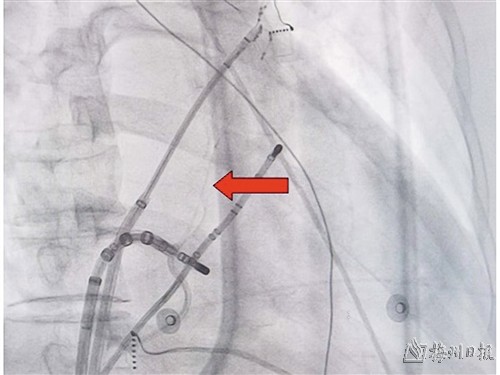

实施Marshall静脉无水乙醇化学消融,箭头所指为Marshall 静脉。(医院供图)

团队反复讨论后决定使用无水乙醇Marshall静脉心外膜化学消融联合房颤导管射频消融术式为患者治疗。在张伯的心衰基本控制之后,完成房间隔穿刺及左房建模和电压标测, 经下腔静脉将导管送至冠状窦内行选择性造影可见Marshall 静脉显影;沿导丝将微导管送入Marshall 静脉远端封堵,将无水酒精注Marshall 静脉内;接着进行房颤三维导管射频消融术。